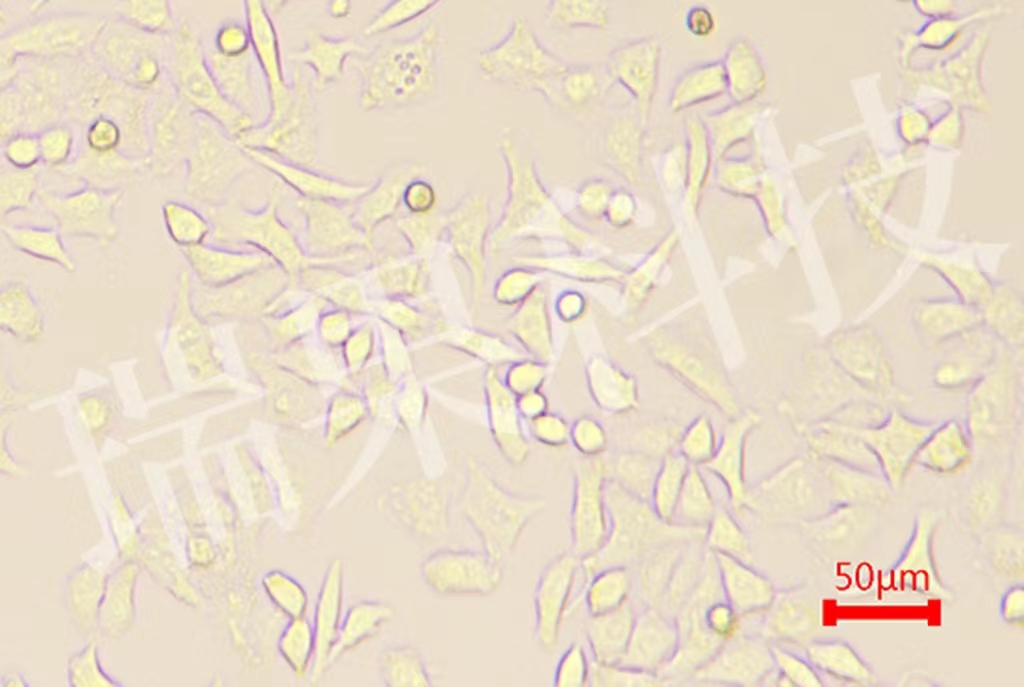

• 肿瘤模型

提供全面、专业的肿瘤动物模型构建与研究服务,覆盖从基础研究...

肿瘤模型